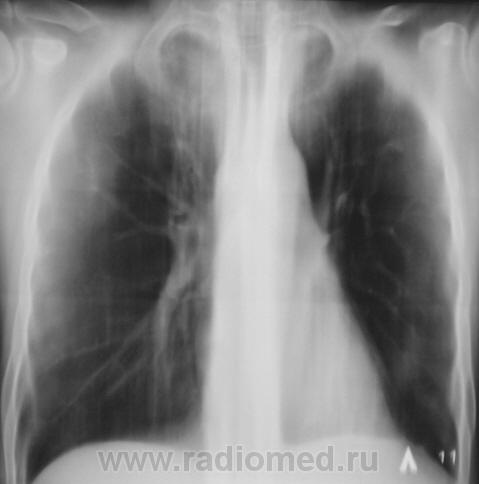

Контроль после флюорографии.